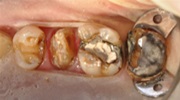

当医院におけるアマルガム治療例

強度のあるアマルガムを使うと上の写真のように歯自体をビルドアップ(盛り上げて歯冠部を製作する)することが出来ます。